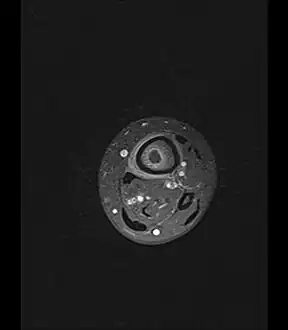

Axial T1-weighted MRI pre-contrast enhancement showing that the intramedullary collection is T1-hyperintense suggesting proteinaceous viscous fluid consistent with infection. -

Axial T1-weighted fat-saturated MRI image following IV gadolinium contrast demonstrating the intramedullary lytic area seen on radiography to be ring enhancing consistent with a purulent fluid collection. Extensive circumferential periosteal enhancement is noted. There is also substantial bone marrow enhancement. -